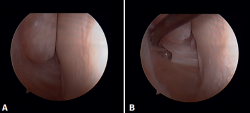

Arthroscopic evaluation of the syndesmosis

From the anteromedial portal we can directly visualize the distal fibers of the ATFL. Disinsertion of these fibers does not always result in instability of the syndesmosis, but it does require us to check it. In our experience, we prefer assessment of the coronal plane of the syndesmosis. We introduce the arthroscope into the tibiotalar joint directing the camera cranially. In this way we have a direct view of the distal tibiofibular joint. We then assess stability by attempting to insert the palpation probe into the joint. If it is possible to do so, we classify the syndesmosis injury as unstable (Figure 6A).

Arthroscopic evaluation of the deltoid ligament

There are multiple methods for assessing instability of the medial complex; using the anterior ankle portals it is possible to assess the stability of the deltoid ligament in its main plane of action, corresponding to the coronal plane. Chun et al.(20) described instability when it is possible to introduce an arthroscopic palpation probe into the medial tibiotalar space (Figure 6B). Vega et al.(21) reported that, in the majority of injuries, the most anterior portion of the deltoid ligament is detached from the medial malleolus, while its proximal insertions remain intact. In this situation, the arthroscopic palpation probe can be inserted between the medial wall of the internal malleolus and the deep fibers of the deltoid ligament.

Figure 6. Maneuvers to demonstrate ligament instability. A: lesion of the syndesmosis allowing insertion of the palpation probe into the distal tibiofibular zone; B: lesion of the deltoid ligament allowing insertion of the probe into the medial tibiotalar space.